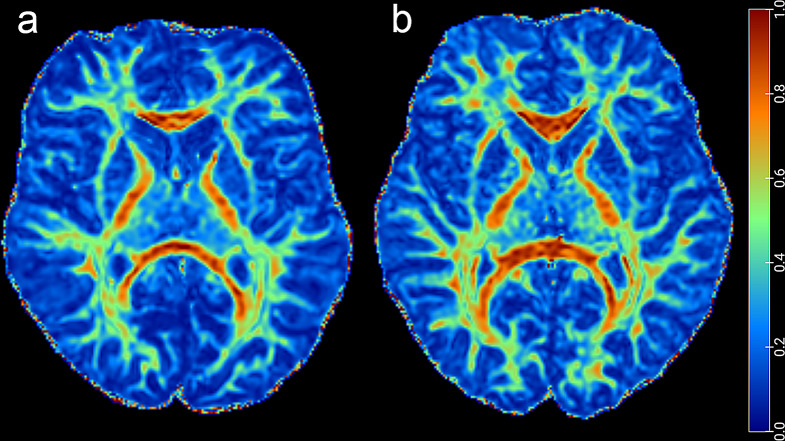

Methods: Forty-two type 2 and 3 pediatric SMA patients and 42 age- and gender-matched healthy controls (HC) were prospectively enrolled in this study. The tract-based spatial statistics (TBSS) was used to assess white matter integrity and the structural network properties were calculated based on DTI white matter fiber tracking and the graph theory approach. A partial correlation was performed to explore the relationship between white matter parameters and clinical characteristics.

Results: In total, 42 patients (mean age, 10.86 ± 4.07 years; 23 men) were included. TBSS analysis revealed widespread white matter changes in SMA patients. The SMA patients showed changes in multiple small-world and network efficiency parameters. Compared to the HC group, SMA showed increased characteristic path length (Lp), normalized clustering coefficient (γ), small-world characteristic (σ), and decreased global efficiency (Eglob) (all p < 0.05). In the node properties, right supramarginal gyrus, right orbital part of superior frontal gyrus, right supplementary motor area, and left median cingulate and paracingulate gyri changed in SMA patients. A decreased axial diffusivity (AD) value was associated with lower Hammersmith Functional Motor Scale-Expanded scores (r = 0.45, p = 0.02), which means that the symptoms of SMA patients are more severe.